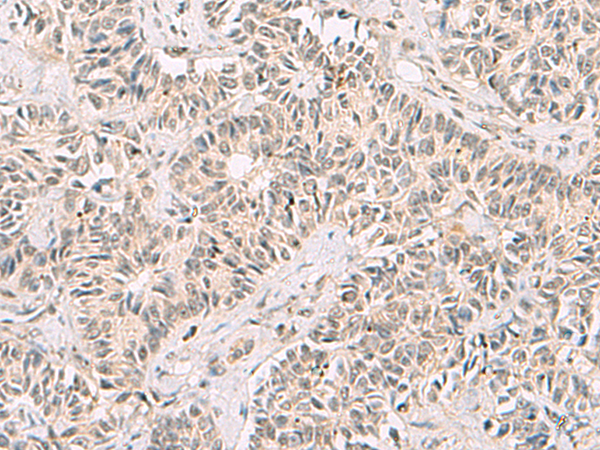

分类: 科研抗体货号: P10095别名: TEF5; TEAD5; TEF-5; DTEF-1; ETFR-1; TEAD-3应用: IHC反应种属: Human, Mouse